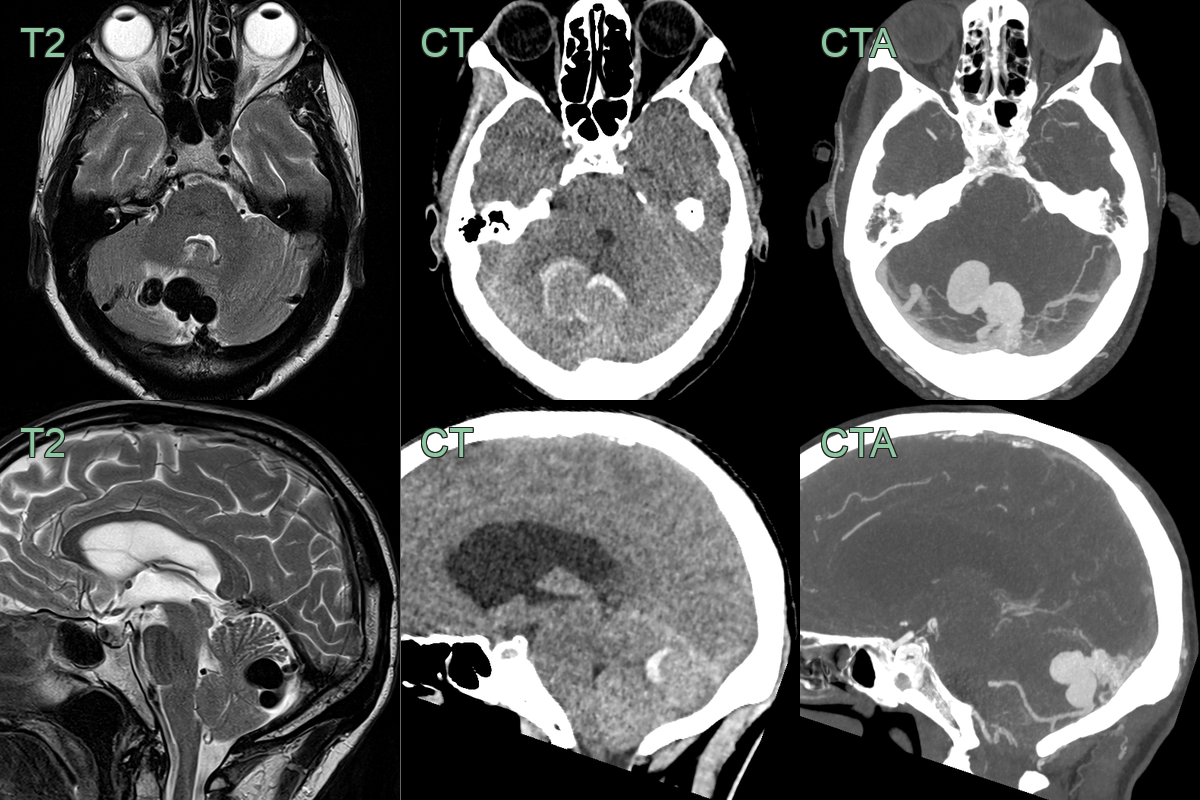

- An MRI on admission showed a dilated vessel in the posterior fossa with a rim of edema within the cerebellum.

- Immediately after the MRI, the patient's headache worsened and an CTA showed hemorrhage around the dural arteriovenous fistula that was supplied by the PICA.